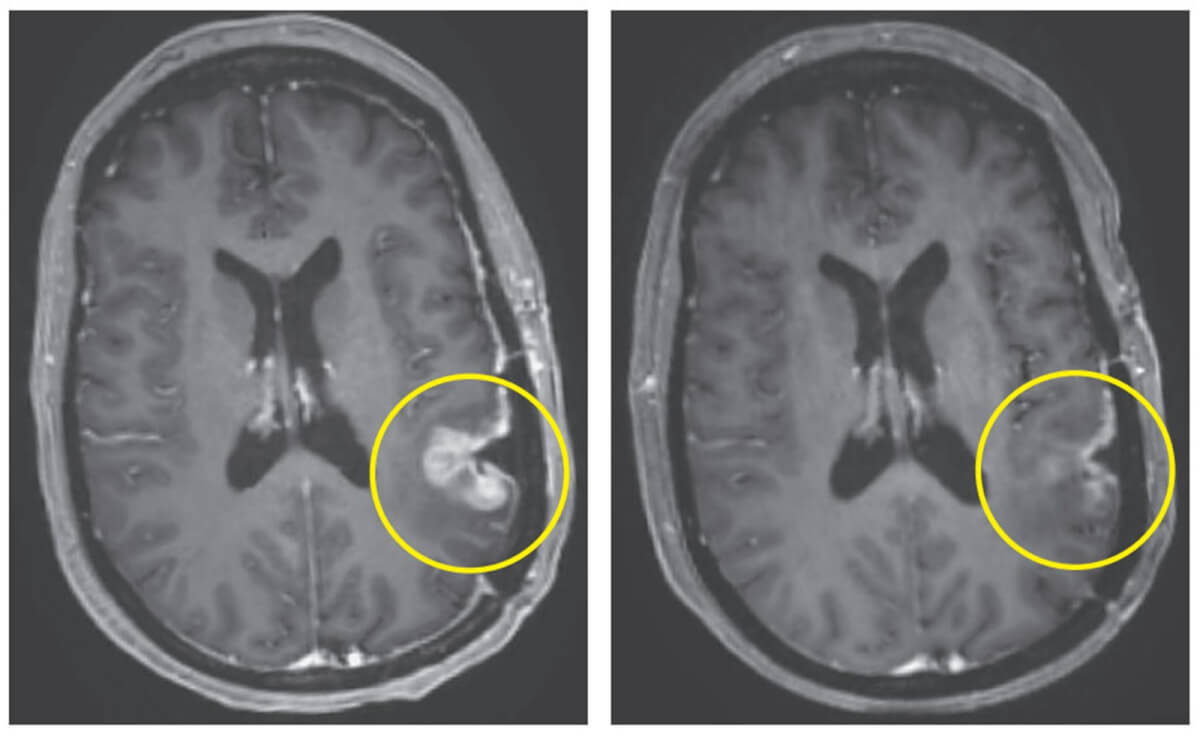

MRI results from Participant 3, before infusion (day -7) and after infusion (day 5) (Credit: Mass General Brigham)

Although nearly all participants experienced fevers and changes in mental status shortly after the infusion, they generally tolerated the procedure well. Remarkably, just days after a single treatment, the patients saw significant reductions in their tumors, with one patient achieving nearly complete tumor regression within five days.

One of the patients, a 72-year-old man, saw an over 60-percent decrease in his tumor which was sustained for six months, while a 57-year-old woman had near complete tumor regression only five days after a single infusion.